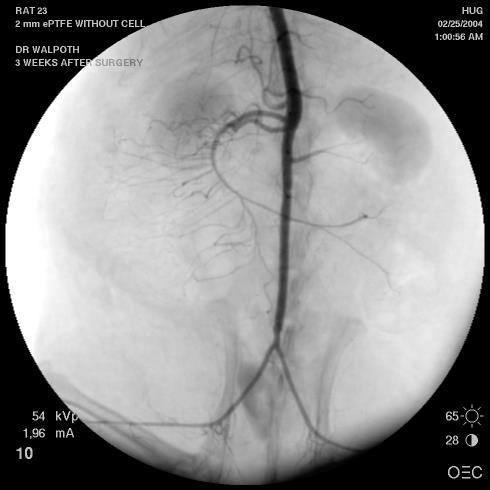

P. Reymond1, D. LaGrange1, O. Felix2, M. Tschopp2, J.-P. Giliberto1, R. Marchi1, T. Jbilou1, J-Ch. Tille1 , O. Jordan1, N. Murith1, M. Cikirikcioglu1, V. Garibotto1, M-L. Piallat1, G. Decher2, P. Fontana1, B. Walpoth1, C. Huber1

1 University & University Hospital, Geneva, Switzerland, 2 University of Strasbourg & C.N.R.S. Institut Charles Sadron, Strasbourg, France

Currently, there is no commercial small calibre vascular prosthesis (internal diameter less than 6 mm) for surgical revascularisations due to poor clinical patency results caused by early thrombosis and late intimal hyperplasia (Abbaszadeh et al , Halbert et al ) We have therefore developed an anti-thrombogenic and cell-favouring Layerby-Layer (LbL) coating

Our dual-action coating is based on end-point attached heparin and cellfavouring LbL coating The coating was applied to small calibre, micro-porous, degradable polycaprolactone (PCL) electro-spun vascular grafts and patches and compared to uncoated samples In vitro coagulation tests (thrombin time / partial thrombin time / anti-Xa assays) and thrombin generation tests up to 7days were made

The in vitro coagulation tests showed no coagulation, and the thrombin generation assay showed no clot formations up to 7-days on the coated patches, compared to thrombus formation (high levels of EPT (nmol/l/m)) for the uncoated patches There was a higher endothelial cell proliferation on the coated patches at 7-days in cell culture as well as a reduction of smooth muscle cells

and 12-weeks (n = 3 per coating and implantation duration) PRE-CLINICAL OUTCOME DATA

This novel dual-action coating has shown good in vitro and in vivo anti-thrombotic and endothelial cell proliferating effects on micro-porous, degradable, vascular grafts.

Application of our coating on clinically used ePTFE grafts show similar promising results in vitro Thus, it could show benefits in clinical revascularization operations such as: coronary, peripheral